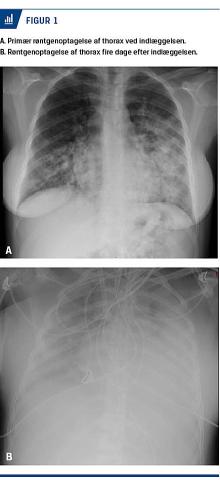

På mistanke om præterm fødsel blev der givet lungemodnende behandling med et højpotent steroid, betamethason, 12 mg × 2. Desuden blev hun behandlet med pivmecillinam på mistanke om cystitis acuta. En urindyrkning viste vækst af Escherichia coli med resistens for pivmecillinam, hvorfor behandlingen blev ændret til cefuroxim. Efter to døgns indlæggelse forværredes hendes respirationsbesvær. En røntgenoptagelse af thorax viste bilaterale infiltrative forandringer (Figur 1A). I tillæg hertil fandt man stigende infektionstal

Trods optrappet respiratorbehandling forværredes hendes respiratoriske tilstand yderligere, og på grund af desaturation til under 66% blev der på tredje døgn på maternel indikation udført akut sectio i generel anæstesi. Operationen var kompliceret, idet patienten flere gange desaturerede til under 50%, og med en pO2 på 5,58 mmHg blev der iværksat behandling med veno-venøs ekstrakorporal membranøs oxygenering (ECMO) (Figur 1B). Herefter rettede saturationen sig til 100%, og patienten blev overflyttet til Aarhus Universitetshospital.